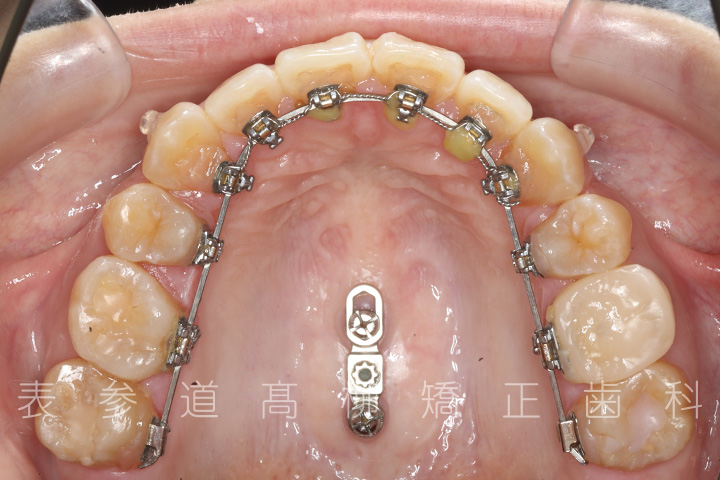

・マウスピース型矯正装置と歯科矯正用アンカースクリュー(i-station)を併用し、上顎臼歯部を圧下

・歯科矯正用アンカースクリュー(i-station)を併用し、前歯部を後方へ移動する

・歯科矯正用アンカースクリューを併用し、口下顎大臼歯の近心移動(前方への移動)

・マウスピース型矯正装置による嚙み合わせの微調整

・リンガルブラケット装置

・歯科矯正用アンカースクリュー